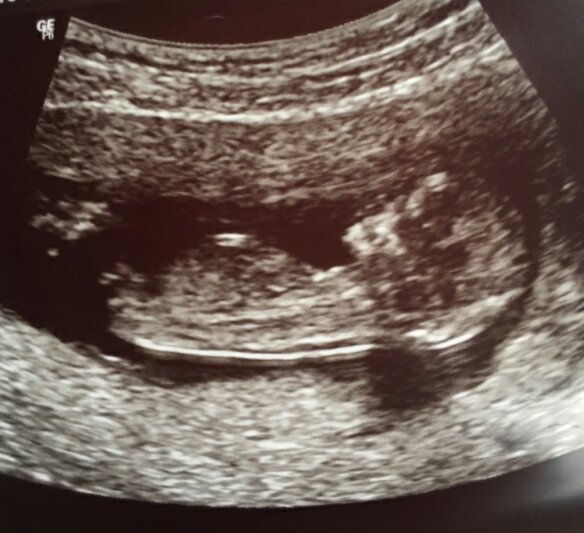

Hello all. I have a good idea on my baby's nub but looking for some expert opinions. Any feedbAck would be greatly appreciated :)

Boy? The nub looks like it's angled up a bit.

Leaning girl. What is the gestation here?

12+2. Iv been told the bit that is sticking up is part of leg and not part of nub. X

A bit earlier than I like to guess, but still thinking girl! Good luck :happy:

With your picture, the overall shape, look and angle just look girl to me.

Early but girly lean.